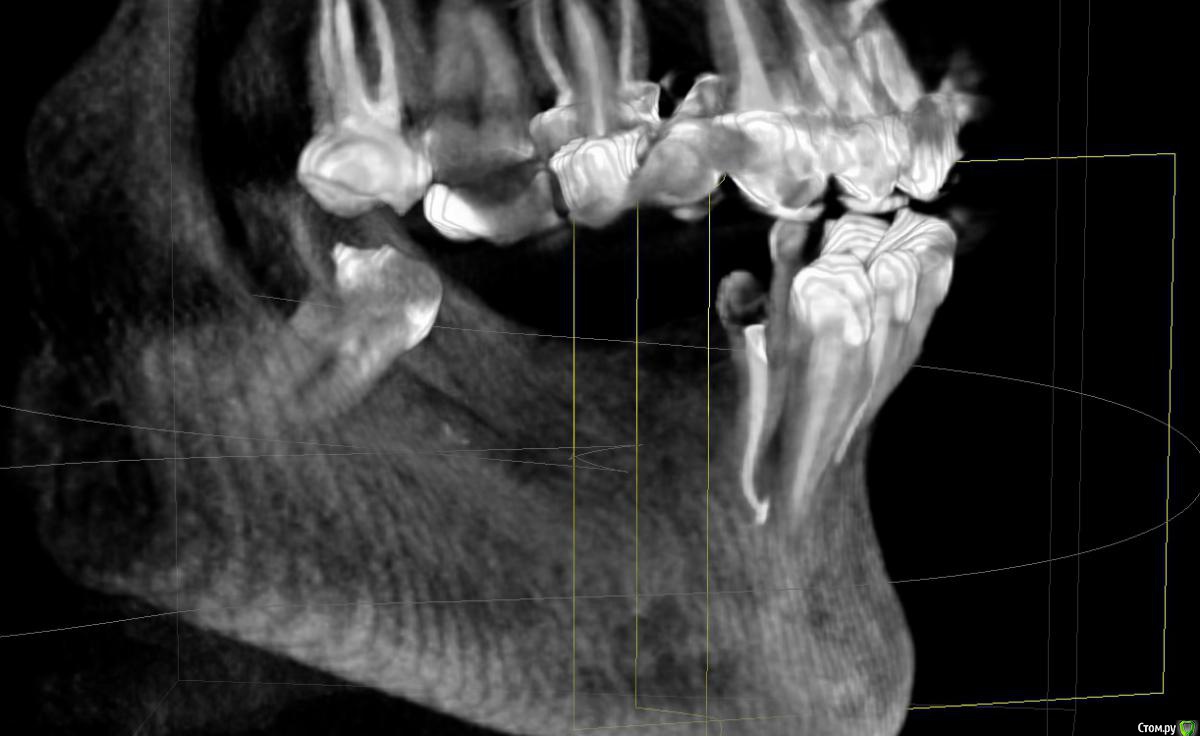

Прошу совета по плану остеопластики с дальнейшей имплантацией (на нижней челюсти).

53 года. Необходимо протезирование нижней челюсти.

Все врачи говорят о недостатке костной ткани (3мм).

Все говорят о необходимости удалить 4-ку слева (так как большая киста, зуб спасти невозможно). Вопросы по поводу дальнейших действий и общей стратегии протезирования.

Слева и справа делаем расщепление гребня, потом слева ставим 3 импланта, справа - два.  Передние зубы не депульпируем (так как они маленькие (сильно сточенные) и их надо не обтачивать, а наращивать., на них коронки. Восстанавливаем зубной ряд по 7-ки включительно.

О расщеплении врач говорил, как о процедуре, у которой практически не бывает неудачных вариантов. Этот вариант малотравматичен. и вообще замечательный.

Снимки месячной давности (8-ка уже удалена). Прикус на этом снимке не видно, нижняя челюсть смещена внутрь по отношению к верхней (не знаю, важно ли это)

я попыталась сделать принтскрины с 3D, но, к сожалению, не очень понимаю, какие снимки (углы, ракурсы) нужны, может быть сделала не то и не так, сорри. Понимаю, что скачивать 3D времени у большинства нет.

post-48869-0-20530400-1472582105_thumb.jpg

post-48869-0-99232900-1472582231_thumb.jpg

post-48869-0-09101500-1472582237_thumb.jpg